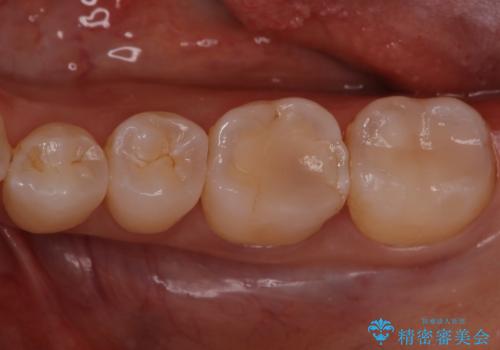

銀歯を無くしたい セラミックインレー

- 銀歯が気になるということで来院された患者様です。

セラミックでの治療を希望されたので治療をいたしました。

銀歯は長い間使用していると隙間ができて、虫歯の原因になります。

そのため適合の良いセラミックをお勧めいたします。